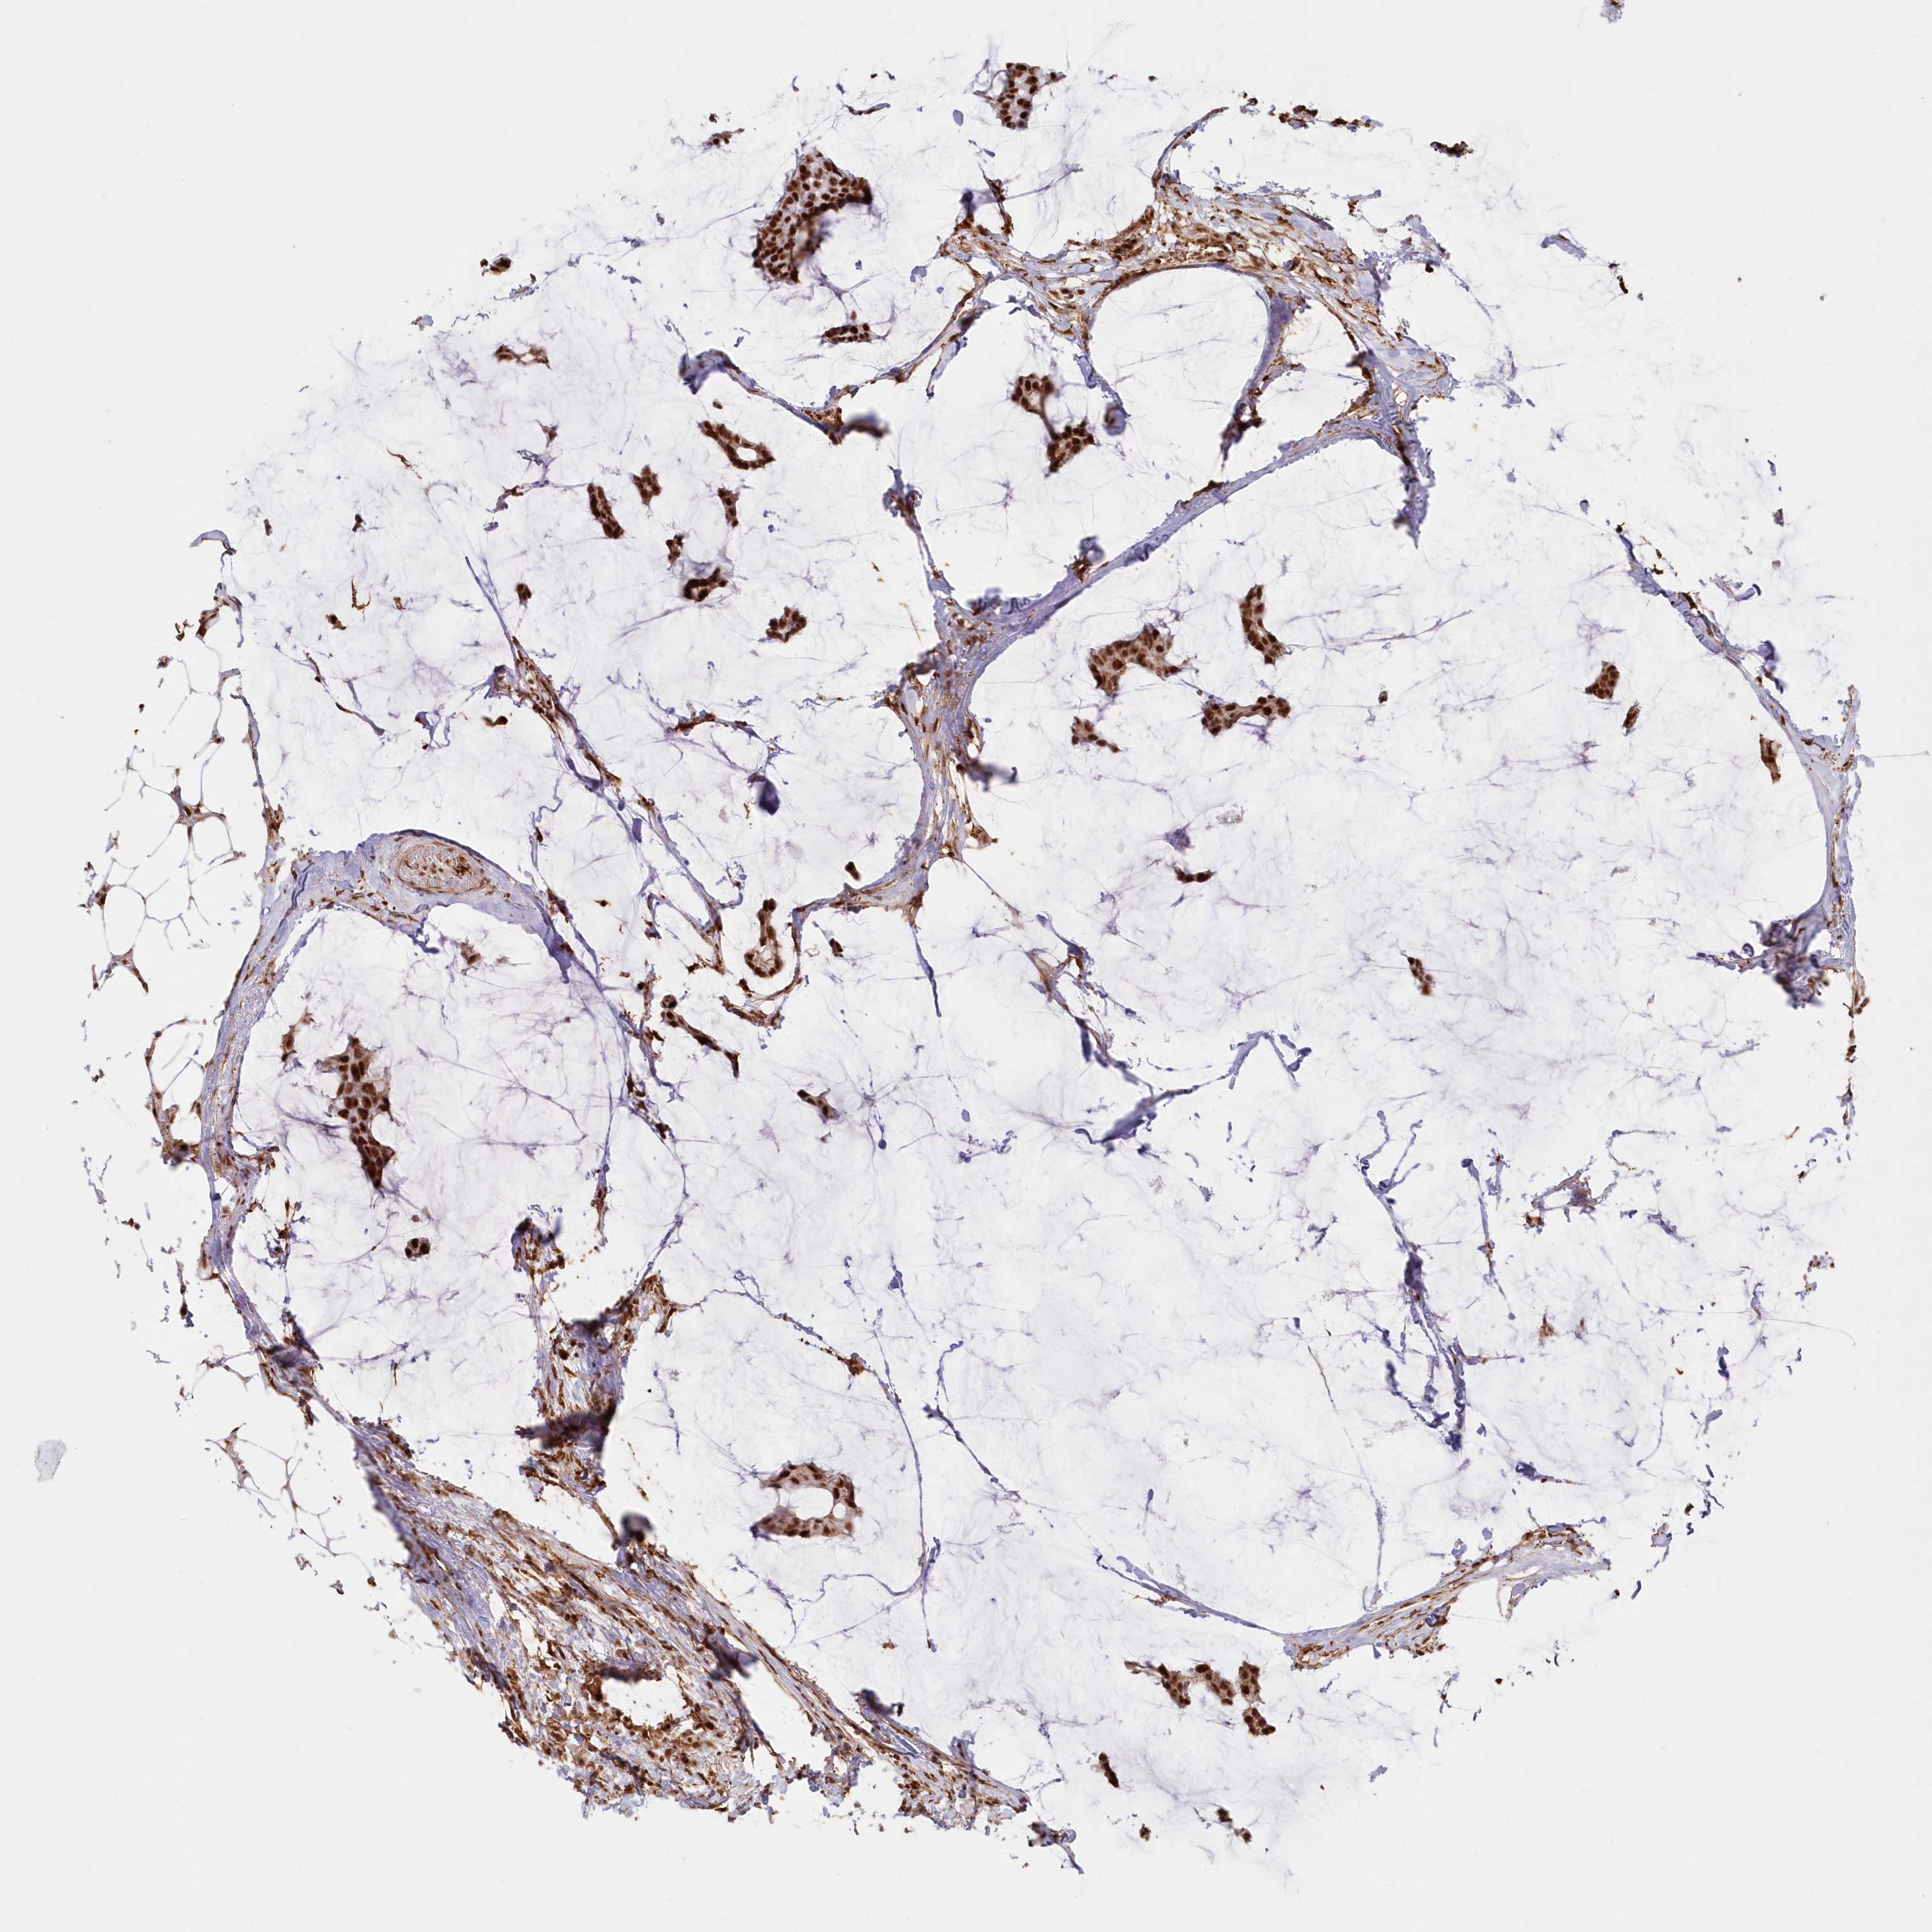

Breast cancer

Human cancer